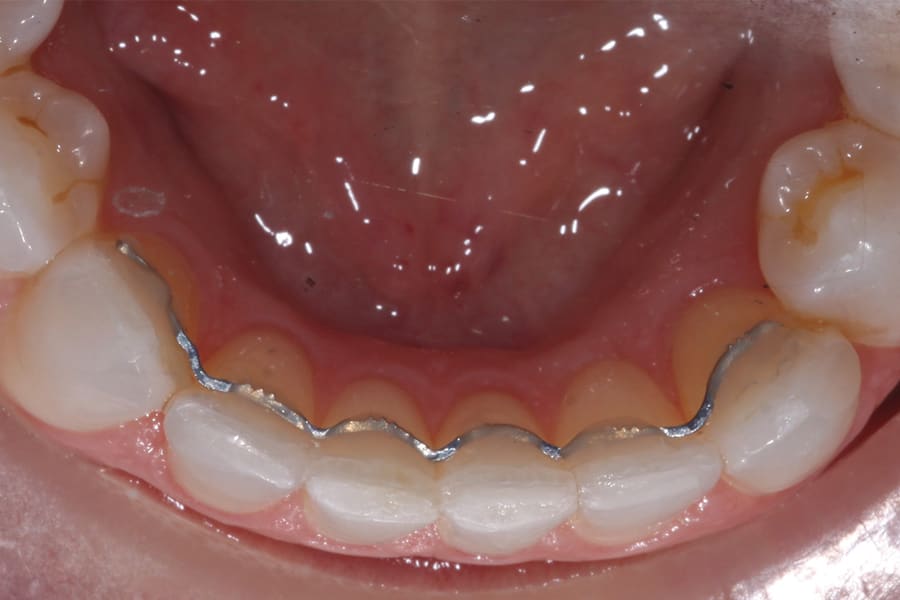

Fixed lingual retainers are customarily placed in the anterior region, on either or both arches. Consideration must be given to overbite and overjet for the maxillary arch to prevent occlusal interference. A deep bite case usually precludes the use of a maxillary fixed retainer. Bonded lingual retainers are designed to extend from cuspid to cuspid most frequently, but can also include first bicuspids or be made shorter to extend over fewer teeth when appropriate, depending on the pretreatment condition.

Early fixed lingual designs consisted of a thick stainless-steel wire (.025" to .032") bonded to the cuspids only (once banding became obsolete) and resting against the lingual surfaces of the incisors. However, when incisal movements (such as derotations) are accomplished, more secure stabilization of each tooth is preferable. Consequently, more streamlined designs bonded to each tooth have gained favor.

Conceptual features have driven the design of proper lingual retainers. The idea is to employ a wire that has enough strength and, more importantly, memory to accurately stabilize a tooth in its desired position while also allowing for some flexibility and physiologic mobility during function. In this way excessive forces (when chewing) are absorbed and bond failure is less likely when compared to a completely rigid design. However, if the fixed retainer is not completely passive when bonded it will impart active forces on the teeth over time.

A popular example of this approach is the twisted stainless-steel wire retainer (Figure 1). This design features ease of fabrication and placement as well as minimal cost. Frequently, a twisted lingual retainer can be fabricated chairside and placed immediately with no preparation, impressioning, or laboratory fabrication required. Consequently, this design is commonly utilized. It can be made from a very thin wire (such as a .009" ligature tie) that is folded over and spun down (or twisted) then formed to the arch curvature and direct bonded. Annealing the formed wire prior to placement can be beneficial, as this can remove the "memory" that stainless steel possesses if not permanently deformed.

Obviously, more suitable and reliable fixed lingual retention designs are needed, and, fortunately, many are available. As described above, the twisted chairside fabricated design can be unreliable. A well-suited alternative is a passive braided design as shown in Figure 2 (Ortho FlexTech® stainless steel, Reliance Orthodontics, relianceorthodontics.com). The braided design does not uncoil over time. The lingual retainer is placed in passive fashion after being cut to the proper length from a spool and bonded to the appropriate teeth. This relatively inexpensive alternative is fabricated chairside with no laboratory intervention or special preparation required. One potential downside is that it is a relatively bulky option.

A second alternative is a laboratory-processed nickel-titanium splint (Figure 3) (Memotain®, AOA Lab, aoaaccess.com). The splint is manufactured via laser etching from a sheet of material conforming to a digital impression that is sent to a laboratory. Because the wire is not bent from stock, it is passive in nature and has no uncoiling tendency. It conforms accurately to tooth surfaces and is comfortable due to its streamlined design and intimate conformity. These characteristics also make it suitable as a splint when teeth are imperfectly aligned, as in a periodontally involved crowded dentition (Figure 4). Drawbacks of this design are the time and expense of laboratory fabrication.